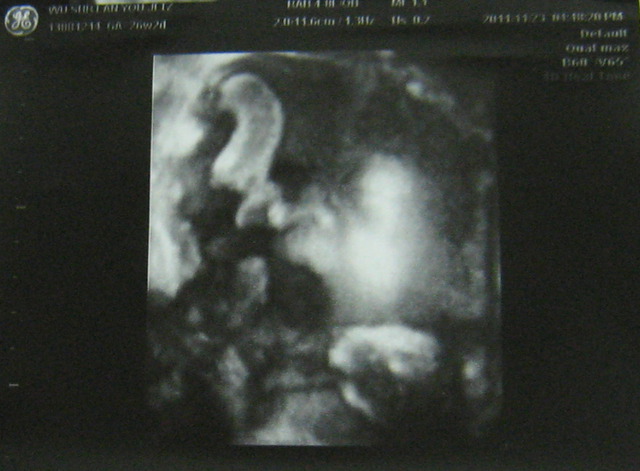

有,次也做4D,然我看到的是模糊的影像,但有次看到瓦力正在打哈欠?的子,我得好好玩,也很多人有看胎在肚子打哈欠(嘴巴)的子,所以跟大家分享。往下看就找到喔。